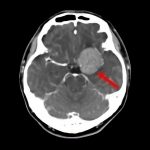

134

'19年10月

70代

左側頭葉膠芽腫

頭蓋内腫瘍摘出術

No.’19_35 手術前1

No.’19_35 手術前2